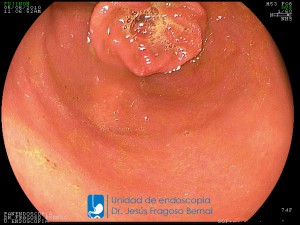

La Unidad de Endoscopía fue creada en 2002 por el Dr. Jesús Fragoso Bernal, es pionera en el estado por la utilización de la tecnología más avanzada, que nos permite ofrecer servicios integrales de diagnóstico y tratamiento para las enfermedades del aparato digestivo.

"La Unidad de Endoscopía se ha caracterizado por un progreso continuo desde su inicio marcando la pauta en los procedimientos endoscópicos en el estado de Tlaxcala y estando siempre a la vanguardia tecnológica."